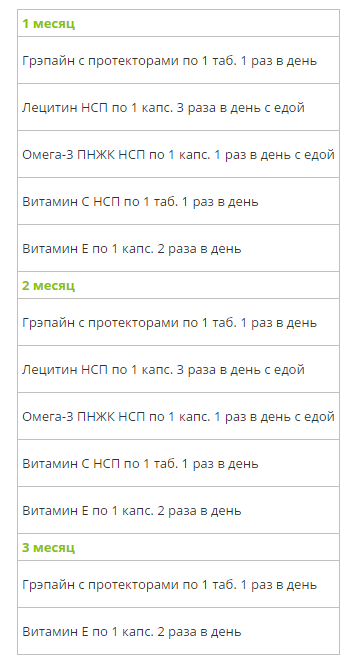

Предлагаем две схемы приема данного набора:

— Если у Вас нет клинических проявлений нарушений в работе сердечно-сосудистой системы, и Вы хотите принимать данный набор в профилактических целях, используйте 3х месячный курс.